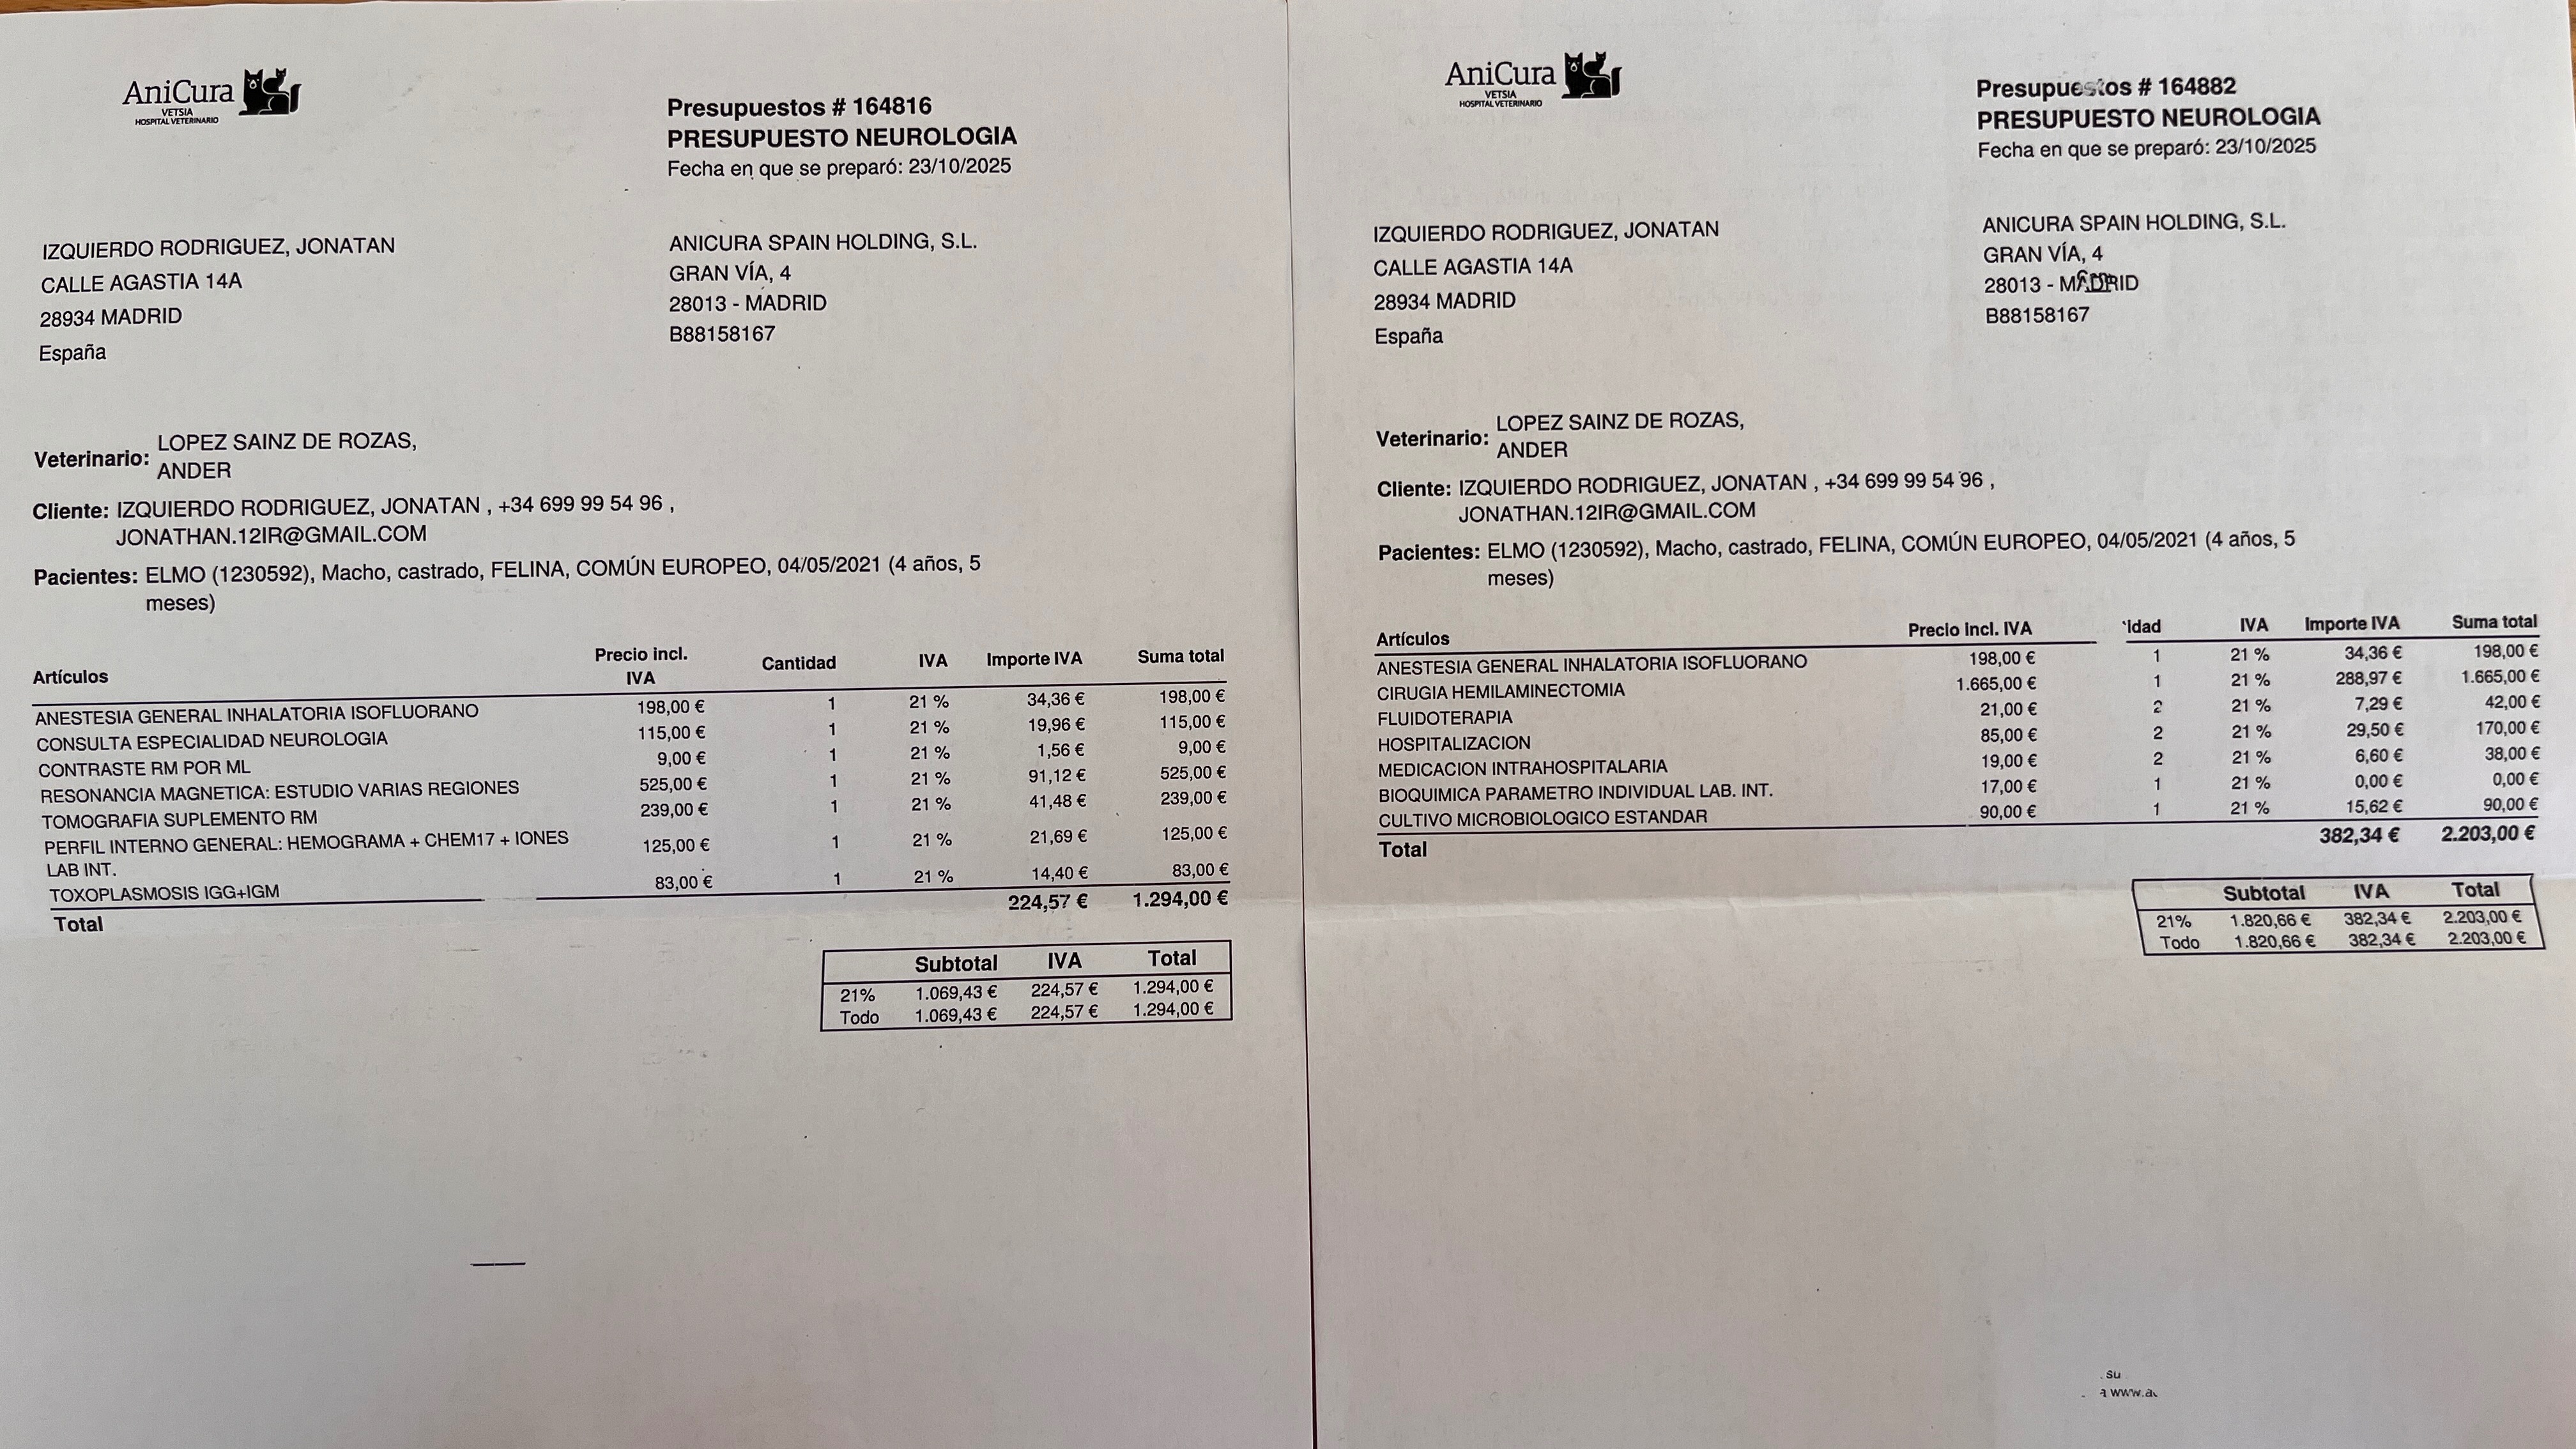

Hace una semana, alguien del vecindario le disparó con una escopeta de perdigones en la puerta de casa. No es la primera vez que ocurre. Esta vez, la herida fue tan grave que Elmo perdió la movilidad de las patas traseras y, tras varias pruebas, ha tenido que ser operado de urgencia para tratar una infección en la médula, donde habían llegado restos de metralla.

Las radiografías muestran varios perdigones antiguos y nuevos. Durante los primeros días apenas podía moverse, no controlaba sus necesidades y tenía la mirada perdida. Poco a poco se está recuperando, pero el proceso es largo y los gastos veterinarios ya superan los 3.500 €.

Pedimos ayuda para cubrir parte de estos costes y continuar con su tratamiento y rehabilitación.